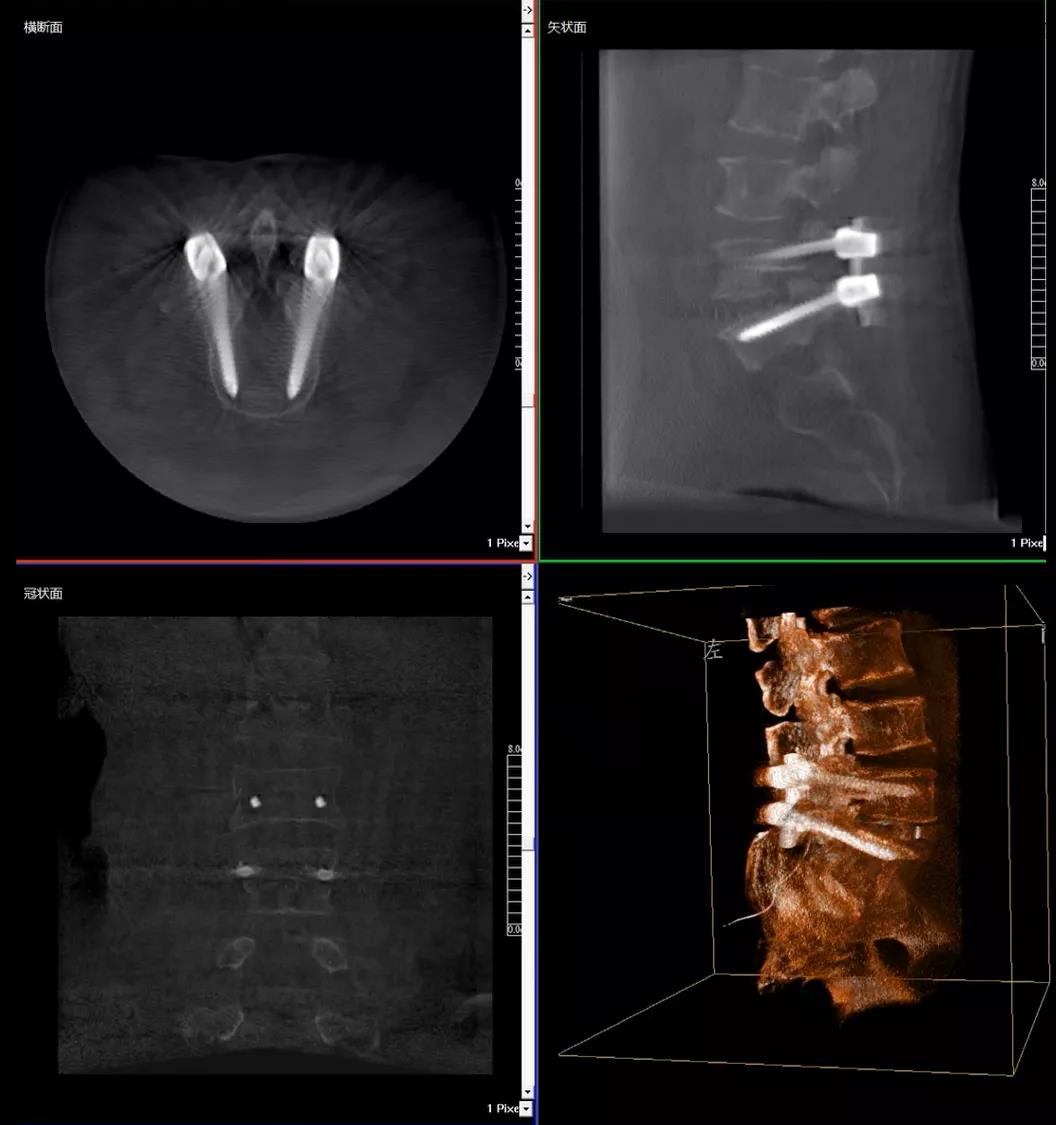

患者1:女性,56岁,L5/S1椎间盘椎板减压+钉棒固定术

患者下腰部疼痛,活动受限,伴有左下肢疼痛5年,久站或弯腰干活时疼痛加剧,卧床休息后疼痛症状缓解,近一个月情况加重,需行椎板减压+钉棒固定术。

医生在影像引导下在L5/S1椎弓根处打入医用螺钉

术中快速生成横断面、矢状面、冠状面断层图像和三维立体图像